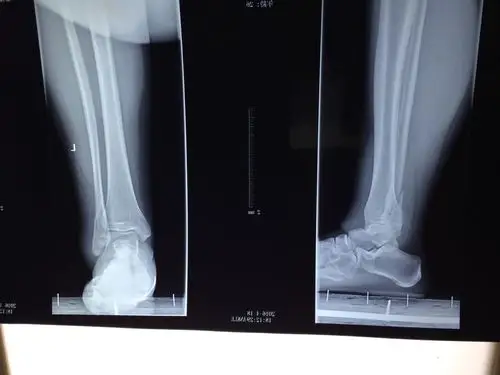

医学影像 摔伤致左小腿下段疼痛,活动受限,x线见腓骨骨折, - 抖音

腓骨下端骨折

清明节左腿胫腓骨下端粉碎性骨折4月7号做了手术

62岁腓骨下段粉碎性骨折锁定钢板系统内固定手术一例

2岁小孩不慎被自行车碾压后致左胫腓骨下段骨折

自己穿高跟鞋跑的,转弯不小心摔跤了,请问左腓骨下端及后踝骨折,断端

前段时间腓骨下端骨折了两个月后重新照片是这样的前一张是复查的

胫腓骨下段骨折闭合复位髓内钉内固定加腓骨下段锁定钢板内固定手术一

左胫腓骨开放性骨折

左腓骨踝关节端骨折由于患者年级较大身体状况较差平时走路

小腿左胫腓骨中下段粉碎骨折,保守治疗.

腓骨骨折